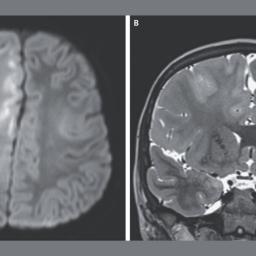

Story ImageA new case report illustrates the deadly impact of subacute sclerosing panencephalitis, a rare complication of measles infection.